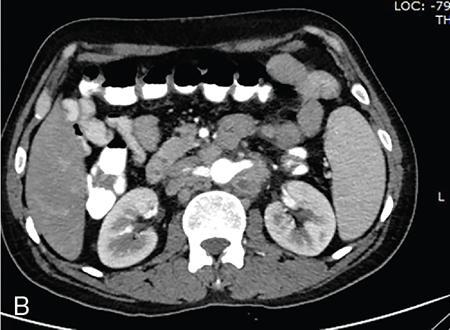

Vijay Kumar K.R. CONGENITAL SPLENIC ABNORMALITIES A multitude of variants and pathologies affect the spleen and it is pertinent for a radiologist to be aware of the common imaging appearances of the same. The spleen begins to develop in the fifth week of gestation from a mass of mesenchymal cells that condense between the two leaves of the dorsal mesogastrium. Several such aggregates fuse to form the lobulated embryonic spleen. The spleen is translocated to the upper left side of the abdominal cavity due to rotation of the stomach and differential growth of the dorsal mesogastrium. The mesogastrium fuses with the peritoneum over the left kidney and forms the splenorenal ligament. The lienorenal ligament fuses dorsally and the splenic artery courses behind the peritoneum as it enters the splenorenal ligament. The portion of dorsal mesentery between the stomach and spleen forms gastrosplenic ligament. Differentiated mesenchymal cells form the parenchyma, connective tissue and capsule of the spleen. The foetal spleen shows lobulations, which normally disappear before birth. However, they may persist along the medial part of the spleen. Sometimes a persisting portion of the spleen may extend medially and anteriorly over the upper pole of the left kidney. It may be mistaken for a space-occupying lesion arising from the kidney. Rarely it may extend posterior to the upper pole of the left kidney, displacing it anteriorly (Fig. 9.22.1.1). The notches and clefts along the superior borders are vestiges of the grooves that initially separated the foetal lobules. They may be 2–3 cm deep. They may mimic a splenic laceration in a patient with abdominal trauma, and the embedded peritoneum at the waist may simulate splenic infarction or haematoma. Hence caution should be exercised. A normal spleen which does not have a fixed ligamentous attachment can change position within the abdomen and is hence known as a wandering spleen. The spleen is normally anchored by the gastrosplenic and lienorenal ligament. Absence or weakness of one or more ligaments that affix the spleen. The spleen with its vascular pedicle as the sole attachment can become a hypermobile intraperitoneal organ. Rarely, the spleen may be normal in position with a wandering accessory spleen. Pregnancy (due to hormonal effects), prune belly syndrome, splenic cysts, malaria, Hodgkin’s disease and lymphangioma. Some of the affected patients may be asymptomatic and diagnosis may be incidental. Clinically it presents as a mobile, palpable, notched mass. Pressure on the vascular pedicle or torsion causes symptoms such as acute abdominal pain, nausea and vomiting. Torsion involving the tail of the pancreas may present as pancreatitis. Confirms the absence of spleen in the left upper quadrant of abdomen with identification of splenic tissue at an ectopic site. Power Doppler, colour Doppler and duplex sonography allow for the identification of blood flow in the splenic vessels and parenchyma. Intermittent torsion may be responsible for an enlarged spleen. Pathognomonic feature of wandering spleen is absence of the spleen in the upper abdominal cavity and presence of a well-demarcated, homogeneously enhancing mass of soft tissue in the pelvis or abdomen. Sometimes a wandering accessory spleen can be visualized as a long vascular pedicle connecting a small mass to the splenic vessels (‘jokari sign’). It can locate ectopic splenic tissue and can also indicate the viability of the tissue. Splenic vessel anatomy can be well demonstrated. 99mTc-sulphur colloid scintigraphy and heat denatured 99mTc-labelled red blood cell imaging provide useful information regarding size and location of splenic tissue. Torsion is indicated by lack of tracer activity in a previously demonstrated wandering spleen. Twisting and torsion of splenic artery can be demonstrated by celiac arteriography. The venous phase may demonstrate splenic vein obstruction with collateral circulation and varices. A congenital focus of normal splenic tissue that is separate from the main body of the spleen is known as an accessory spleen. It results from the failure of fusion of some embryonic splenic buds within the dorsal mesogastrium. Its incidence varies from 10% to 30% on autopsy examinations. They vary from a few millimetres to several centimetres in diameter. They most commonly are found around the splenic hilum. The second most common location is the pancreatic tail. They can also be found in the stomach wall, omentum, mesentery, large bowel and scrotum. Reveals a round or oval mass of tissue around the splenic hilum that is isoechoic with the main spleen. On noncontrast images they are isodense to the main spleen. CECT reveals serpiginous enhancement on arterial phase followed by homogeneous enhancement on venous phase-like spleen (Fig. 9.22.1.2). Accessory spleen is mildly hypointense to the spleen on T1 images and isointense on T2 images. Contrast administration reveals enhancement similar to that of spleen on the arterial, portal and late phases. It is isointense to spleen on DWI images with similar ADC values. 99mTc-sulphur colloid scintigraphy and heat denatured 99mTc-labelled red blood cell imaging show functional uptake in splenic tissue and differentiate splenule from other masses. PET CT-FDG avid mass can mimic tumour. Surgical resection is the preferred mode of treatment in the background of hypersplenism or lymphoma. It is characterized by an ectopic splenic tissue or an abnormal connection between the gonad and the spleen. The left side is more commonly involved than the right side. The accepted theory is that splenic gonadal fusion occurs due to abnormal attachment of the splenic anlage in the left dorsal mesogastrium with the left urogenital fold, during the fifth to eighth weeks of gestation. It has a higher male preponderance and can interfere with left testicular descent and closure of processus vaginalis. It commonly presents as inguinal hernia and cryptorchidism. The spleen and gonad are attached by a fibrous or splenic cord across the peritoneal cavity. It is associated with limb defect syndrome, cleft palate, micrognathia, anal anomalies, craniosynostosis, spina bifida, cardiac malformations, thoracic malformations and diaphragmatic hernias. This is not associated with congenital anomalies. Shows a well-defined scrotal mass with echotexture similar to that of spleen. Confirms splenic tissue in inguinal or scrotal area. It is characterized by the absence of spleen with duplication of right-sided structures. (Right isomerism). It has a slight male preponderance with an incidence of 1 in 40,000 live births. It has a poor prognosis due to its high association with congenital cardiac abnormalities (Fig. 9.22.1.3). It is of uncertain aetiology, and maybe associated with the mutations of CFC1 gene, SHROOM3 gene etc. Delayed development of embryonic curvature can be another cause. It is also theorized that it can be caused due to vascular compromise by pressure on splenic blood supply from adjacent structures. Splenectomy – Usually has a surgical history and is not accompanied by associated anomalies. It is a heterotaxy syndrome associated with multiple spleens and duplication of left-sided structures. (Left isomerism). It has an equal gender predilection with a slightly higher female preponderance. It has a fairly better prognosis than asplenia and is associated with a lesser incidence of cardiovascular anomalies (Fig. 9.22.1.4). It is of uncertain aetiology, and maybe associated with the mutations of CFC1 gene, SHROOM3 gene etc. Accelerated development of embryonic curvature can be another cause. SPLENIC INFECTION AND ABSCESS The infection of the spleen can show three patterns. Fungal and granulomatous infections usually present with multiple micronodules. A pyogenic abscess usually manifest as a solitary lesion. Imaging of diseases causing splenic nodules is never the sole basis for diagnosis. The clinical presentation and laboratory testing (tumour markers, tuberculosis testing and bone marrow biopsy) help in establishing an accurate diagnosis. The imaging findings are nonspecific and the nodules may vary in size from a few millimetres up to 2 cm in diameter. They maybe hypoechoic on ultrasound and hypoattenuating on CT. They are of low signal intensity on T1-weighted sequences and vary from hypointense to hyperintense on the T2-weighted sequences. The nodules show no enhancement or show ring enhancement after contrast study. Healed granulomas are seen as scattered, discrete, small calcifications in an otherwise normal spleen. With increasing number of immunocompromised patients, such as oncology patients undergoing aggressive chemotherapy, critically ill patients in intensive care units, injection drug abusers, and HIV-infected patients, there is rise in the incidence of splenic abscess. For splenic abscess to develop, it may require the presence of bacteremia (sepsis and septic emboli) and altered splenic architecture, which is caused secondary to a haematoma, infarct, or sickle cell disease. Abscesses can also develop from the extension of infection from adjacent organs, like in cases of infected pancreatitis and perinephric abscess, which are less common. In about 20% of cases, cause or source could not be discovered. Abscesses can be unilocular or multilocular, solitary or multiple, depending on the causative organisms and patient’s immunity. Mortality ranges from 15% in otherwise healthy patients with unilocular splenic abscess to 80% in immunocompromised patients with multiple abscesses. Abscesses which are multilocular, gas-containing or due to gram-negative bacillus show poor prognosis. A pyogenic abscess is usually solitary, unilocular/multilocular, but it can also be multifocal. These are uncommon and are reported in 0.14%–0.70% of large autopsy series. Most common presentation is fever (92%), left upper abdominal pain (77%) and leucocytosis (66%). Other symptoms are left pleural effusion and splenomegaly. It can be solitary or multiple, unilocular or multilocular. The appearance of splenic abscess depends on the stage of development. In the early stages of the disease, an abscess appears as an ill-defined mass later developing into a complex collection with septations, debris and sometimes gas. In later stages, after a capsule is developed, the lesion becomes well defined. Left pleural effusion is seen in around 42% of cases. Left lung base atelectasis in 20% of cases and splenomegaly is seen. Abscess with air can be identified based on the presence of extraluminal gas or air–fluid levels in the left upper quadrant. Ultrasonography has a sensitivity of 75%–98% in detecting splenic abscess. This is a very useful modality in patients who are bedridden, with renal impairment and for assessment of small splenic lesions (Fig. 9.22.2.1). Ill-defined hypoechoic mass mimicking a mass is seen in the early phase of the infection and a complex mass with internal septations, debris, rarely acoustic shadowing caused by gas is seen in later stages. The capsule appears as a thin hyperechoic rim. It is noninvasive, speedy, and a modality with high sensitivity (92%–98%). It helps in differentiating unilocular from multilocular lesions and, gives exact anatomical localization and information about perisplenic area, which later helps in planning-guided management procedures. An abscess is seen as a hypodense collection or complex cystic lesion with enhancing rim on the postcontrast study (Fig. 9.22.2.2). CT may help in identifying concurrent areas of infection and, thus, the source of infection. On CT, an abscess may look similar to an infarct, haematoma, or neoplasm. An infarct lacks mass effect, unlike abscess or tumour (Fig. 9.22.2.3). The presence of gas within the lesion is diagnostic of abscess; however, this finding is rare. Splenic abscesses show low signal on T1-weighted images and high signal on T2-weighted images compared with the normal spleen. Minimal to intense peripheral enhancement is seen after IV administration of gadolinium. But MRI is not routinely done, as many patients are clinically unstable. This plays a limited role in the detection and localization of splenic abscess. A nonspecific filling defect is seen on a 99mTc-sulphur colloid scan within spleen if the size is more than 2 cm in diameter. Normal inherent splenic activity on 67Ga scans and 111In-labelled leukocytes scans obscures any kind of inflammatory focus in the spleen, giving rise to false-negative examination. 67Ga scans are nonspecific as tracer uptake can be seen in neoplastic conditions such as lymphoma. Detection and characterization of the abscess are better done if 99mTc-sulphur colloid scan is done prior to 111In-labelled leukocytes scan. FDG PET/CT can also detect the site of infection but not used in the diagnosis of splenic abscess. Early diagnosis of an abscess is prompted for a better outcome. Based on laboratory findings, appropriate antibiotic therapy initiated. USG or CT-guided percutaneous aspiration is tried if the abscess is less than 5 cm in size, and for larger abscesses, percutaneous drainage procedures are done preserving the spleen. Splenectomy is reserved for complicated infections. Fungal abscesses are usually seen in immunocompromised patients with neutropenia such as patients with acquired immunodeficiency syndrome (AIDS), on chemotherapy and immune suppressive agents, and with lymphoproliferative disorders. With the advent of aggressive chemotherapy, the incidence of splenic fungal infections has increased. Approximately 7% of patients with acute leukaemia have hepatosplenic fungal infections. Multiple microabscesses are common. Hepatosplenic candidiasis lesions are very small, and before the advent of CT and MRI, their detection was too difficult. They measure in the range of 5–10 mm in diameter; however, they may be even miliary (<5 mm). Infections are mostly caused by candida species. Other organisms are aspergillus, Histoplasma and Cryptococcus. Imaging characteristics depend on the stage and severity of neutropenia. In cases of chronic disseminated infections with poor neutrophil counts, sometimes lesions are not visible as the host fails to produce an immune response. Lesions become apparent once neutrophil counts improve. Patients presenting with fever and splenomegaly are not improving on conventional antibiotic therapy, and with associated immunocompromised status, fungal infections are to be considered. No single imaging is specific or sensitive in establishing the diagnosis. Serial imaging is needed to detect hepatosplenic involvement; however, tissue diagnosis is the gold standard. Four different patterns are seen in hepatic candidiasis. Multiple, small, homogeneous hypoechoic nodules are the most common finding. Less commonly wheel-within-a-wheel appearance (i.e. the target sign) is seen in the early stage of infection. The first wheel is the peripheral hypoechoic zone of fibrosis and an echogenic second wheel of inflammatory cells around a central hypoechoic nidus containing necrosis and fungal elements. Later these lesions evolve into Bull’s eye lesion where there is a central echogenic focus surrounded by a hypoechoic halo. Lesions become small and hyperechoic with various degrees of posterior acoustic shadowing, with or without calcification, or they may even disappear later in the course of the infection. Splenic nodules are hypodense lesions measuring in the range of 5–10 mm. Only 30% of cases are detected in noncontrast studies. They often have low attenuation, although there can be a focus of high attenuation or a ‘wheel-within-a-wheel’ pattern. Peripheral ring of enhancement is noted in around 70% of cases in the arterial phase of CT, and it is said to disappear on the portal venous phase. There is no significant difference in the detection of the lesions between arterial and portal venous phases of contrast studies. MRI is said to be the investigation of choice for diagnosis of hepatosplenic candidiasis and is superior to CT and USG, especially when short-time inversion recovery sequence is used. MR imaging is also used to monitor the response to antifungal therapy. Based on MRI findings different phases of hepatosplenic candidiasis are described. Lesions are small, measuring less than 1 cm in diameter. They show mildly hypointense on the T1-weighted images and markedly hyperintense on the T2-weighted images. In 2 weeks to 3 months, acute lesions are transformed into subacute lesions. The lesions reveal mildly increased signal on both T1- and T2-weighted sequences. On all sequences, a peripheral ring of very low signal intensity is seen. Following the gadolinium administration, the central region of the lesions show enhancement; however, the peripheral ring continues to have low signal intensity, making them more obvious. It takes from 3 months to more than 1 year for the healed fungal foci composed of fibrous tissue of differing densities and degrees of vascularization to appear on MRI. The lesions measure 1–3 cm, become irregular, and the central area disappears. Chronic healed fungal abscesses have low signal intensity on T1-weighted images and are isointense to mildly hyperintense on T2-weighted images. No perilesional dark ring is noted. These lesions are moderately hypointense on early postgadolinium images and minimally hypointense on delayed postgadolinium images. Mycobacterial tuberculosis infections are mainly seen in immunocompromised patients. Spleen involvement is seen in disseminated, miliary infection in about 80%–100% of autopsy cases; however, it is documented less on imaging. Splenic tuberculosis is seen in the form of nodules measuring ∼ 0.2 and 1 cm in diameter. The macronodular form is very rare (Fig. 9.22.2.4). Hypoechoic pattern is seen. Hypoattenuating nodules with lymphadenopathy noted. Depending on the different stages of the tubercular process, intensities on T1- and T2-weighted images vary. On contrast-enhanced T1-weighted images, lesions most often show peripheral enhancement less commonly gradual peripheral enhancement with complete filling is noted. It is also called as Mycobacterium intracellulare infections. These are also typically seen in immunocompromised patients. Splenomegaly with multiple, low attenuation nodules is seen. Associated findings such as hepatosplenomegaly, diffuse jejunal wall thickening and enlarged lymph nodes are seen. Lymph nodal involvement is homogeneous as opposed to Mycobacterium tuberculosis infections. Focal splenic or hepatic lesions are noted in about 30% of patients with HIV who are infected with M. tuberculosis but are rarely noted in those infected with M. avium intracellulare. Marked splenomegaly is more common in M. avium intracellulare than in M. tuberculosis infection. It is a common opportunistic infection in patients with HIV. Extra pulmonary involvement manifested in the form of necrotizing granulomas. Spleen involvement is an incidental finding. When treated the nodules may enlarge and become progressively calcified in a rim like or punctate fashion. Disseminated infection can show punctate calcification in adrenal glands, pleural or peritoneal effusions, that subsequently calcify. Splenomegaly with small hypoechoic lesions with cystic components or tiny, highly reflective, nonshadowing foci or calcified granulomas. The nodules are hypodense. Calcified granulomas are seen in later stages. This is a self-limited disease caused by bartonellae henselae. Hepatosplenic involvement is rare. This disease is to be considered when a patient presents with abdominal pain, fever of unknown origin, and multiple hypodense lesions in the liver and spleen. It is also called as echinococcosis, a disease seen in endemic regions and in patients emigrated from endemic areas. The causative organism is a zoonotic tapeworm echinococcus granulosus. The most commonly involved organs are the liver, lung, peritoneum, kidney, brain, mediastinum and heart. Spleen is rarely primarily involved. Spleen is involved in approximately 2% of cases of abdominal hydatidosis. Spleen involvement is seen in case of an extensive abdominal hydatidosis, like after the rupture of liver hydatid cyst or in cases of systemic dissemination of infection. Larvae of the tapeworm incite an inflammatory response after its entry into the target tissue in the host where it forms a hydatid cysts consisting of three layers. Peri cyst is an outer layer of modified host cells forming a dense and fibrous layer. The middle layer laminated layer and an inner germinal layer made up of daughter cysts, also called as brood capsules. Scolices develop in the brood capsules. The laminated and germinal layer forms the true cyst wall. After the parasites die, the cysts become inactive, may calcify, and undergo fibrosis. Patients present with abdominal pain, splenomegaly and fever. The diagnosis is to be suspected in all patients from endemic areas presenting with a splenic cyst. A World Health Organization Working Group on echinococcosis has a standardized sonographic classification of echinococcal cysts (Table 9.22.2.1). CE, cysticechinococcosis; CL, undifferentiated simple cystic lesions. Radiological appearances depend on the natural aging process of the cyst. Classic imaging characteristics are lost when the cyst becomes secondarily infected. A ring-like or curvilinear calcification noted in the left hypochondriac region. This may represent the calcification of pericyst in later stages of the disease. Ultrasound is an easy and most commonly used for evaluation of a suspected case of abdominal echinococcal disease. It is used for the diagnosis, planning the management and follow-up. Shifting of brood capsules within the cyst causes fine internal echoes, that is ‘The snowflake sign’ (hydatid sand). Detached laminated endocysts may be seen within the cysts, that is ‘The. Waterlily sign’. Mother cysts may be partially /completely filled by daughter cysts. Calcifications with posterior acoustic shadowing are seen in later stages of the disease. CT and MRI are indicated for widespread disease and complications and for planning percutaneous therapy and surgery. Complications of a hydatid cyst include compression of the adjacent structures, cyst rupture, secondary infections, anaphylaxis and fistulization to surrounding structures. A hydatid cyst may be seen as a well-defined, hypoattenuating cystic lesion with fluid-attenuation values and a distinguishable wall. CT is more sensitive for subtle wall calcification. May appear hyperdense because of debris, hydatid sand and inflammatory cells (Fig. 9.22.2.5). In CE 2 cysts, peripherally arranged daughter cysts, completely fill them other cyst. The daughter cysts show lower attenuation than the mother cyst. Type CE 3 lesions are round or oval with occasional calcification and daughter cysts. They usually show high attenuation. Type CE 4 cysts are complex masses. Intravenous contrast administration reveals enhancement of septa and cyst wall. Type CE 5 cysts are complex cystic or solid-looking lesions, and they can be partially or completely calcified. The simple cysts show low signal on the T1-weighted images and markedly hyperintense on the T2-weighted images. The rim sign which is a low signal intensity rim well seen in T2-weighted MRI images is characteristic of hydatid disease. Enhancement of septa and cyst wall is noted after the intravenous administration of gadolinium. On T1- and T2-weighted images, the maternal matrix appears hyperintense relative to the daughter cysts. The collapsed parasitic membranes may show serpent sign or snake sign, which are hypointense on all sequences. Hypointensity on T1- and T2-weighted images are seen in type CE 4 and CE 5 cysts. The imaging findings combined with the clinical, immunologic testing and epidemiologic results, usually provide the correct diagnosis. Seen in cases of tuberculosis, histoplasmosis, less commonly in Pneumocystis jirovecii pneumonia and brucellosis. These are incidental findings usually preceded by hypoattenuating microabscesses. Microabscesses heal with or without preceding regression. More than five calcifications usually represent histoplasmosis, whereas less than five represent tuberculosis. A ring-like calcification is seen in Pneumocystis carinii pneumonia. Any granulomatous infection is more likely to involve other organs such as the liver, kidneys and lymph nodes. Hydatid cysts can show ring-like or curvilinear calcification (Fig. 9.22.2.6). SPLENOMEGALY AND HYPERSPLENISM Splenomegaly is often a nonspecific finding, and there are many causes for splenomegaly. The spleen can grow into large sizes towards right iliac fossa, crossing midline. On average adult spleen measures <11 cm in length,<7 cm wide,<5 cm thick, and weighs approximately 150 g (80–300 g). The size and weight of the spleen decrease with advancing age. Spleen size is significantly influenced by the sex and body height of an individual. Chow et al. assessed 1230 healthy volunteers and found that spleen length and volume were significantly and independently associated with sex, body height and weight. Taller and heavier male individuals have larger and longer spleens. In one study the spleen length in 6% of women, and 26% of men exceeded a strict upper limit of normal of 12 cm. Rosenberg et al. established an upper limit of standard splenic length of 12 cm for girls and 13 cm for boys (≥15 years). Massive splenomegaly is defined as a spleen size greater than 18 cm, is less common and includes haematological disorders and infections (Table 9.22.3.1).